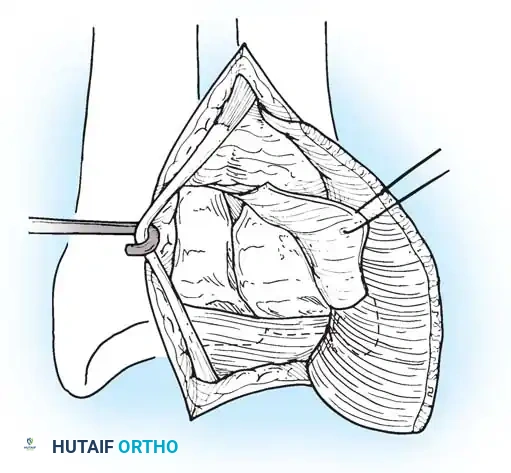

Open repair of the dorsal capsule and TFCC, ensuring robust closure and stabilization of the ulnar-sided structures.

Stabilization of the ECU tendon and subsheath, a critical step in addressing complex ulnar-sided wrist trauma.